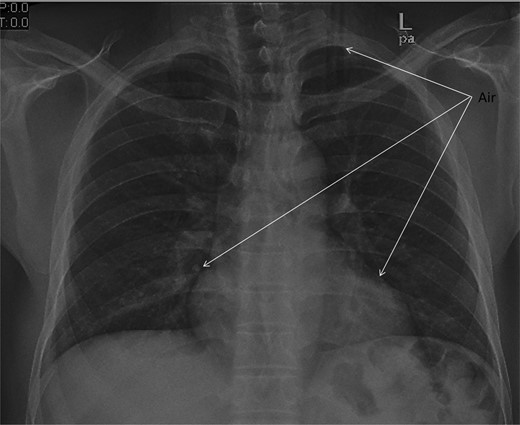

Chest X-ray and head, neck and chest computed tomography (CT) confirmed the diagnosis and extension of PM (Figs 1–3). CT revealed fracture of the floor of left orbit with soft tissue, fat herniation into left maxillary sinus roof, left orbital emphysema with no muscular entrapment. Gas was observed in periorbital tissues, left temporal scalp, infratemporal fossa, left parapharyngeal space and left cheek. Moreover, tissue planes in the neck revealed the presence of air particularly around the carotid vessels, in the posterior triangle and superior mediastinum (PM) around the thymus, trachea (middle), left side of the aorta and anterior to the sternum. However, on auscultation, lungs were clear with and the laryngeal passages and trachea looked normal.

CT scan shows the extension of air from the face, neck and chest.